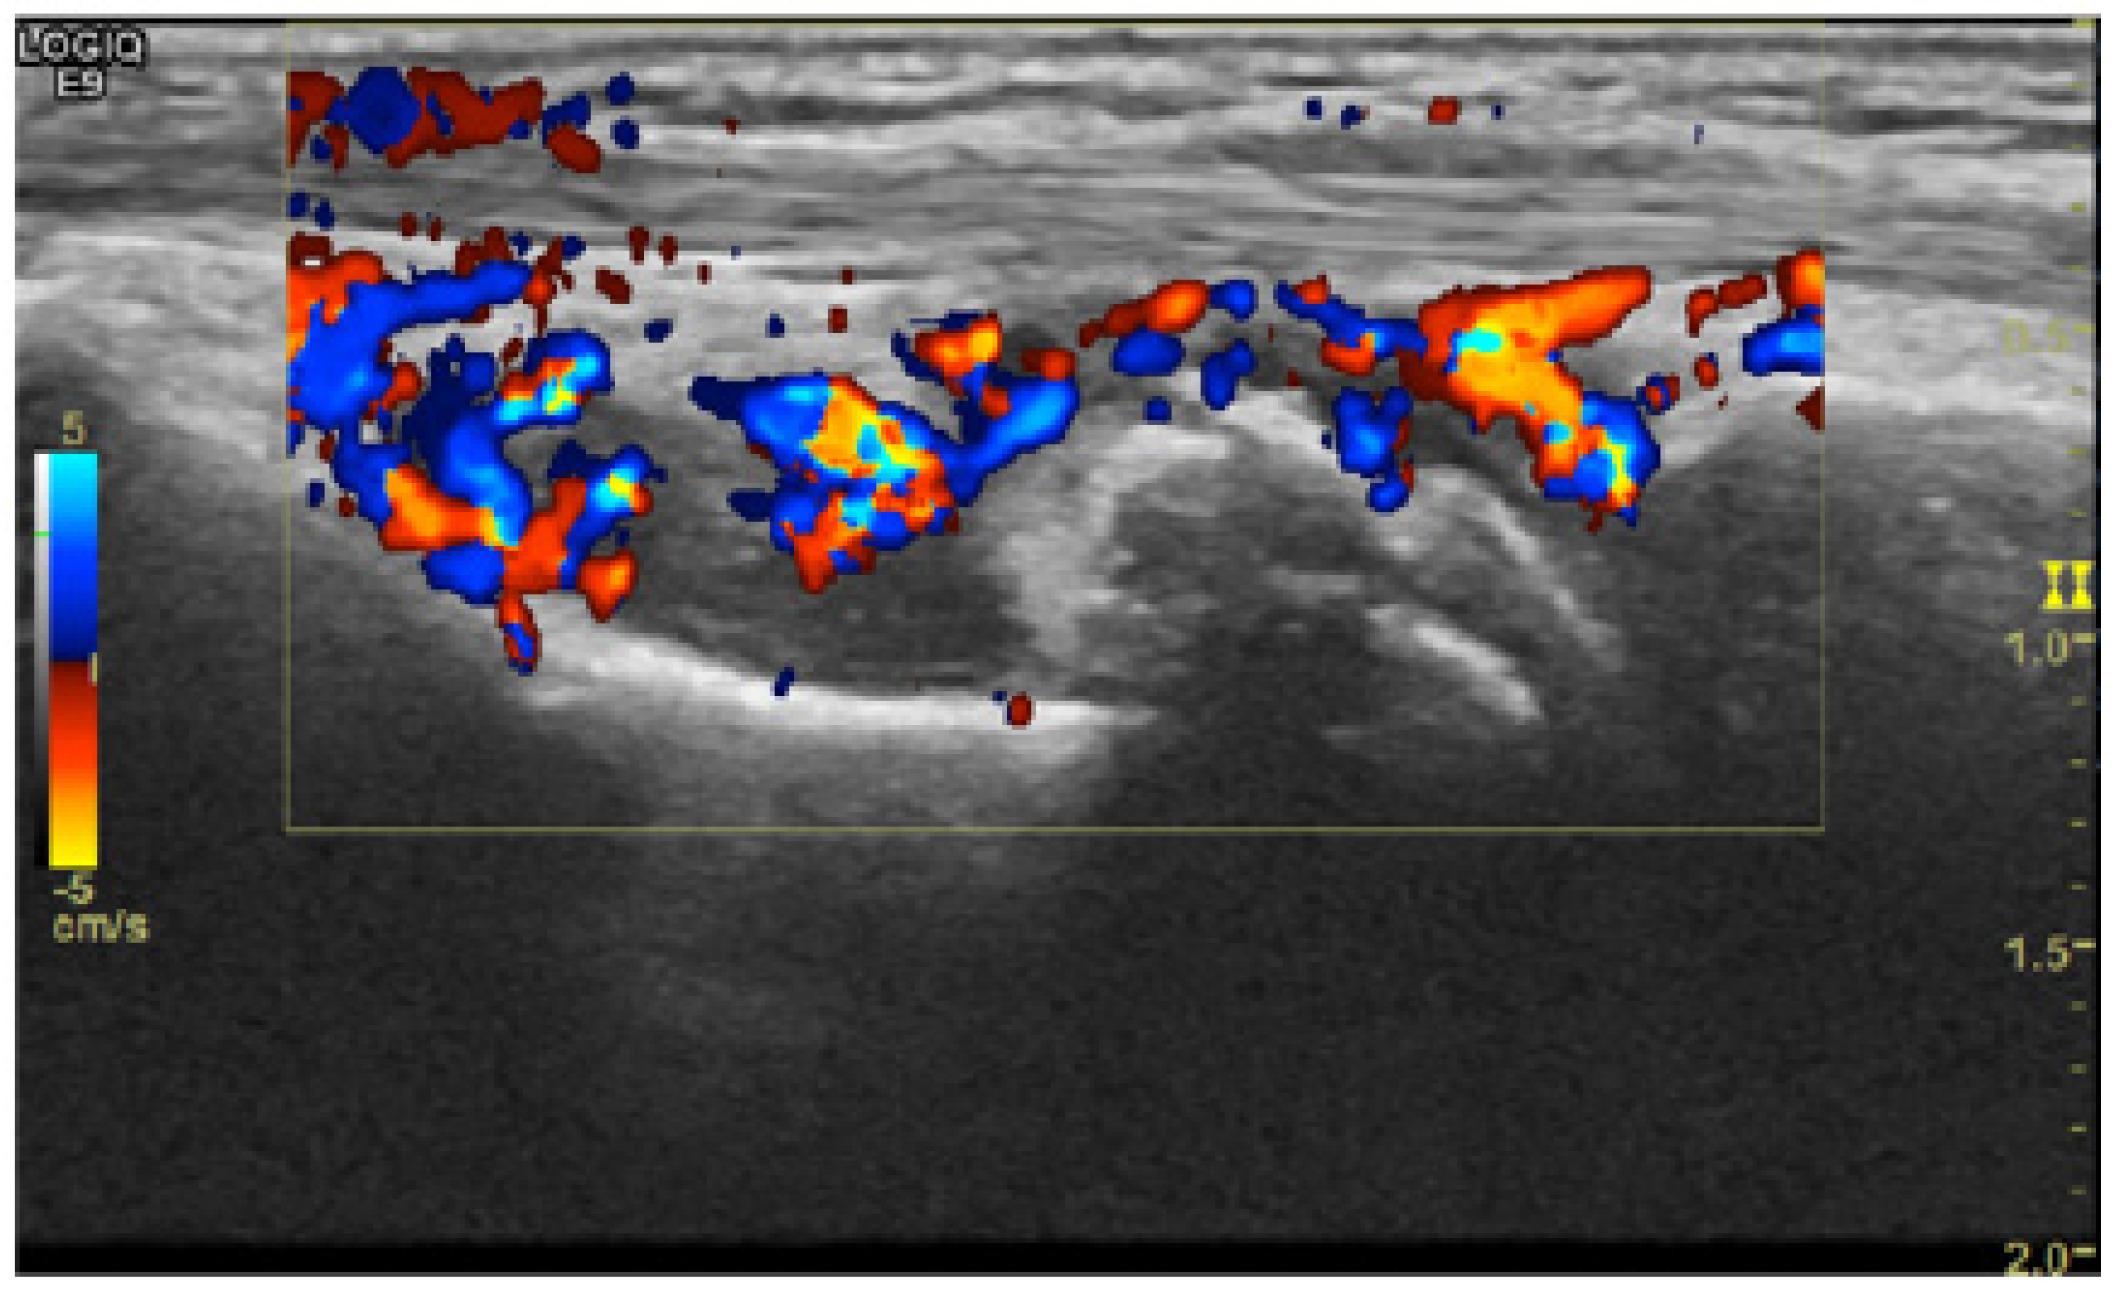

Other authors in [14] engaged with the usage of CNN models for OESS [16] (Doppler mode in US—DUS) system assessment on ultra-sound images for diagnosis and monitoring of patients with RA. They used two state-of-the-art CNN models (VGG16, Inception V3) for two tasks. The first model was used for binary image classification as healthy or diseased (0–1), and the second model was used for OESS score assessment (0–3). The results of the two models were compared with the results of a rheumatologist physician. They created four DUS image sets for each OESS score category. The VGG-16 model was used in order to classify the images of RA joint disease activity as healthy (DUS scores 0 and 1) or diseased (DUS scores 2 and 3). The Inception-V3 model, a more sophisticated model, has a modular architecture as it consists of several modules, the so-called inception modules. Each one of these modules extracts information from the input image following different depths, i.e., different resolutions. The information is then combined in a mixed layer. The first mixed layers contain more generic information in comparison with the latest mixed layers. Then they used the information from the mixed layer with the higher classification accuracy in order to ensemble a classification method where 10 classifiers were trained but with slightly different training parameter settings. The results show that CNN models can be used for DUS image OESS score assessment, as they achieve high accuracy.

As mentioned above, the main modalities of medical images that were used were firstly the radiograph images (Figure 5 and Figure 6) and secondly the ultrasound images (Figure 7 and Figure 8). The authors used datasets that were either created from hospitals and medical centers or were benchmarked datasets such as the RA2 DREAM Challenge Dataset [29] and Medusa Database [30]. Regarding the custom datasets, the dimensions of the original medical images were varied. Furthermore, in some datasets, there were feet images included besides the hand images. According to the model, the original images were resized in order to fit the requirements. In works where there was ROIs detection (e.g., fingers, joints), there was a denoising process performed in order for the model to make the data as “clean” as possible. On the other hand, in works where there were no special ROIs detected, the data were loaded into the model in a raw form but sometimes modified (cropped image with only one hand [23], combination of four images into one showing both hands and feet [12]). It is important to notice that, as the patient data are protected under the scope of GDPR, all patients whose data were used to create datasets at first agreed with the authorities of each institution for the usage of their data. However, even in that way, there were works with datasets that were too small; therefore, a data augmentation method was considered necessary so that efficient data could be created for the demanding training of the models. Moreover, the transfer learning method can solve the problem of limited datasets. Finally, it must be noticed that even with small datasets (e.g., <300 images), some authors achieved good results [16].

Figure 6. Example of an ultrasound color Doppler image of a wrist used in the database of [14].